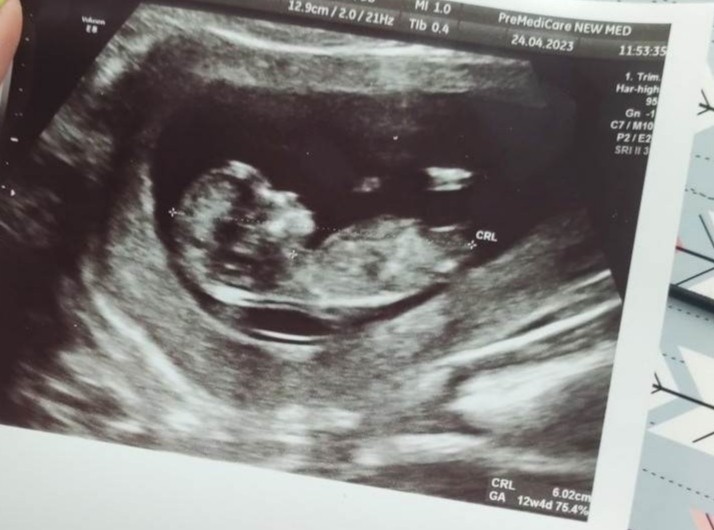

Wyrostek płciowy na usg

Wczoraj prenatalne. Lekarka na podstawie tego czegoś zasugerowała Nam płeć.

To chyba ten wyrostek płciowy.

Jak myślicie kto tam zamieszkuje ? 😊

Tak nam też powiedziala lekarka.

Na grupie ramzi i nub dziewczyny stawiają na chlopaka, ja bardziej mysle o dziewczynce bo właśnie wydaje mi się, że u chłopca bardziej sterczy, ale zobaczymy co wyjdzie 😊

To jest tylko zdjecie z usg. Mysle, ze lekarka miala biezacy obraz i lepiej jej bylo ocenic. Do zdjecia moglo dziecko siw troche poruszyc, inaczej ulozyc. Rozumiem, ze to bylo I badanie prenatalne? Wtedy polowkowe jeszcze przed toba i wtedy lepiej bedzie widoczna plec.

Wg mnie chłopak ale ekspertem nie jestem, podobnie wyglądało "coś takiego" u mnie w pierwszej ciąży przy synku:) Daj znać później co "wyszło".

Tu chyba z tym wyrostkiem chodzi o to że u chlopaka idzie bardziej pionowo, a u dziewczynki bardziej poziomo bo wyrostek jest u każdego 😊